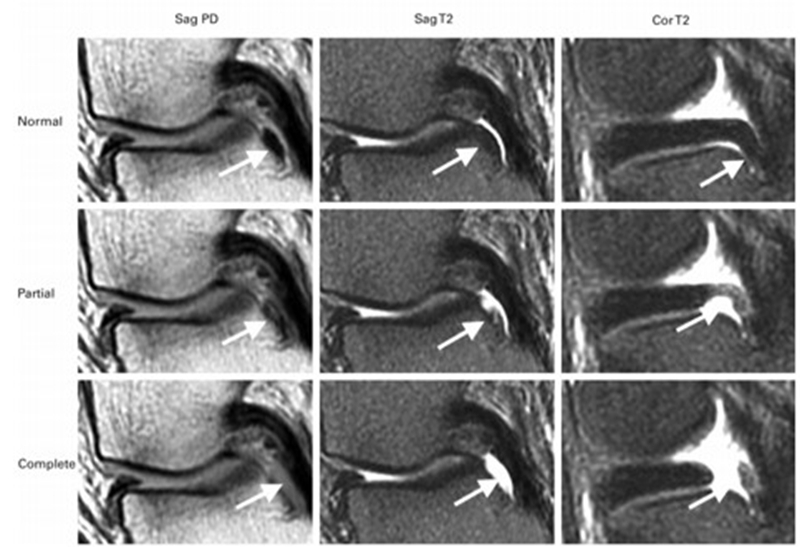

SONK与内侧半月板后根部损伤,有国外学者在SONK患者中通过MRI及关节镜检查,常可发现合并内侧半月板后根部的撕裂,该发生率可达到80%(24/30), 15例完全撕裂,9例部分撕裂。结果表明SONK可能与内侧半月板后根部撕裂后,导致股骨负重区的应力集中、软骨下骨髓水肿有关。